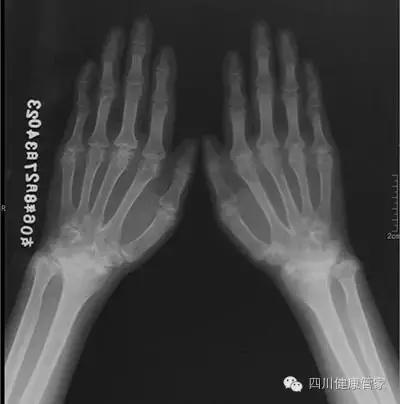

体查双肩关节压痛,抬举、旋后活动受限,双肘、掌指关节肿胀、压痛,左无名指屈曲畸形,双掌指关节迟侧偏移,除无名指外余手指呈“天鹅颈”畸形,右腕关节固定畸形,左腕关节掌曲、背伸受限,右髋关节屈曲畸形,外旋、内旋受限,左髋关节屈曲、内旋活动受限,双膝关节肿大畸形,伸直受限,触之皮温高,双下肢轻度指凹性水肿。舌质黯,苔黄、脉滑数。双膝关节X线示:双膝关骨质普遍疏松,关节间隙变窄,关节面增厚,关节面下可见囊性骨质破坏。

股骨头CT示:双侧髋关节不对称,双侧股骨头边缘不光滑,有缺损,股骨头边缘可见高密度死骨,股骨头内下部可见双边征,以右侧为重。

坚持治疗1年,复查股骨头CT基本正常,膝关节X线示关节间隙稍窄,余未见明显异常,血沉正常,类风湿因子阳性,变天时关节偶有不适,可做一般的家务活。